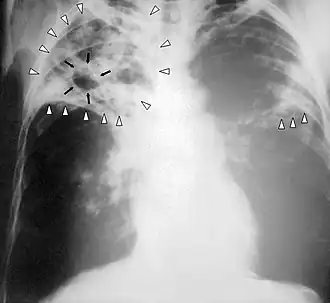

Radiografia ao peito de uma pessoa com tuberculose avançada. As setas brancas assinalam a infeção em ambos os pulmões. As setas pretas assinalam a formação de uma cavidade.

A tuberculose cria cavidades visíveis em radiografias como esta, na parte superior do pulmão direito.

Uma radiografia postero-anterior do tórax é a tradicionalmente feita; outras vistas (lateral ou lordótico) ou imagens de tomografia computadorizada podem ser necessárias.

Em tuberculose pulmonar ativa, infiltrações ou consolidações e/ou cavidades são frequentemente vistas na parte superior dos pulmões com ou sem linfadenopatia (doença nos nódulos linfáticos) mediastinal ou hilar. No entanto, lesões podem aparecer em qualquer lugar nos pulmões. Em pessoas com HIV e outras imunossupressões, qualquer anormalidade pode indicar a tuberculose, ou o raio-x dos pulmões pode até mesmo parecer inteiramente normal.

Em geral, a tuberculose anteriormente tratada aparece no raio-x como nódulos pulmonares na área hilar ou nos lóbulos superiores, apresentando ou não marcas fibróticas e perda de volume. Bronquiectasia (isto é, dilatação dos brônquios com a presença de catarro) e marcas pleurais podem estar presentes.

Nódulos e cicatrizes fibróticas podem conter bacilos de tuberculose em multiplicação lenta, com potencial para progredirem para uma futura tuberculose ativa. Indivíduos com estas características em seus exames, se tiverem um teste positivo de reação subcutânea à tuberculina, devem ser consideradas candidatos de alta prioridade ao tratamento da infecção latente, independentemente de sua idade. De modo oposto, lesões granulares calcificadas (granulomas calcificados) apresentam baixíssimo risco de progressão para uma tuberculose ativa.